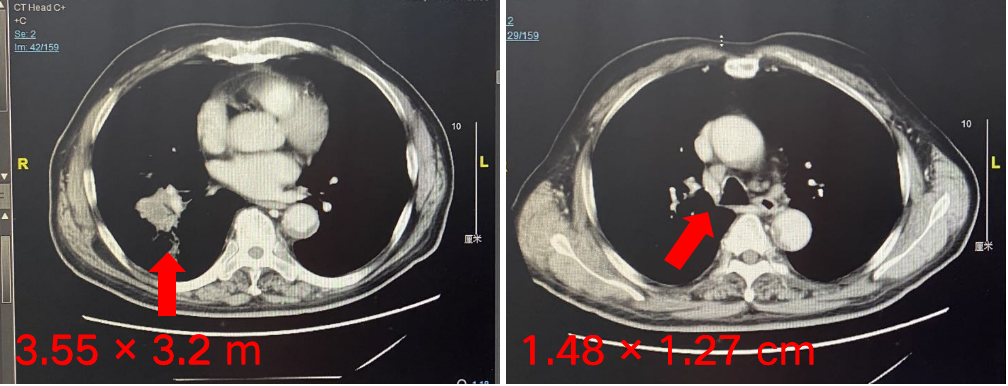

经患者充分知情同意并签署知情同意书后,予以免疫联合化疗方案“替雷利珠单抗200 mg + 白蛋白紫杉醇300 mg+卡铂300 mg,d1,q3w,ivgtt”治疗4周期,疗效达到PR。

本例患者为右肺鳞癌(T4N3M0,IIIC期),伴多发淋巴结转移。经替雷利珠单抗联合化疗治疗,2个周期后右肺病灶和多发淋巴结转移病灶直径均明显缩小,疗效评价达到PR。患者目前已联合用药4周期,疗效持续PR,PFS已超4个月,病情平稳,安全性良好。